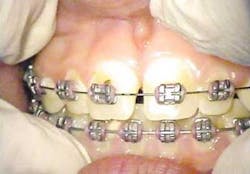

With the dual approach to this procedure, healing at 16 days is profound and complete (figures 8 and 9). Any excess thermal deposition or damage to the tissue is avoided when both lasers are used, and the problematic frenum attachment inhibiting further orthodontic correction is completely removed.